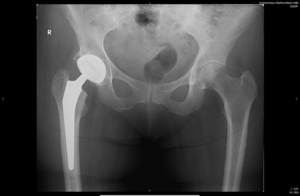

Beim Hüftgelenkersatz verwenden wir unterschiedliche Implantate inklusive der Kurzschaftprothese. Vorzugsweise werden diese, in Abhängigkeit der Knochenqualität, zementfrei eingebracht. Gelegentlich werden teilzementierte Prothesen, sehr selten vollzementierte Komponenten verwendet.

Röntgenaufnahme einer Hüftendoprothese, deutlich sichtbar im rechten Hüftbereich.

Kurzschafttotalendoprothese Hüfte

Röntgenaufnahme einer Hüftendoprothese im rechten Hüftbereich, deutlich sichtbar.

Teilzementierte Totalendoprothese Hüfte